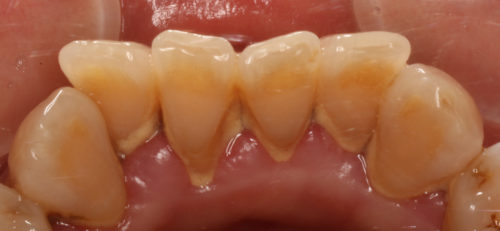

歯石がどれか分かりますか?緑の部分がそうです

下の前歯は特に歯石が付着しやすい部分です

歯石があると、そこにプラークが停滞しやすいため、除去した方が良い

これだけ歯石がついていると、歯と歯の隙間を歯石が“埋めてくれている”

可能性があります

どういう事かと言うと、歯石を除去した後に隙間が見えるようになり

見た目が悪くなったり、物が逆に詰まり易くなる、という事がおきます

ただ、歯周病が進行して抜けてしまうよりは良いですよね・・・